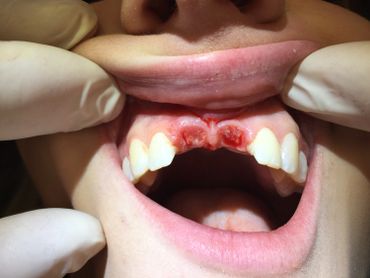

The Neodent GM Guided Surgery Kit is a compact, easy to use guided surgery system. Clinicians can provide CT scan, digital photos, and impressions to a laboratory for precise implant guide fabrication. Temporary teeth can be made and the lab will know the depth, angle, and timing of the connection of the implant. This allows you better esthetics and provides the patient teeth the same day with less chair time.